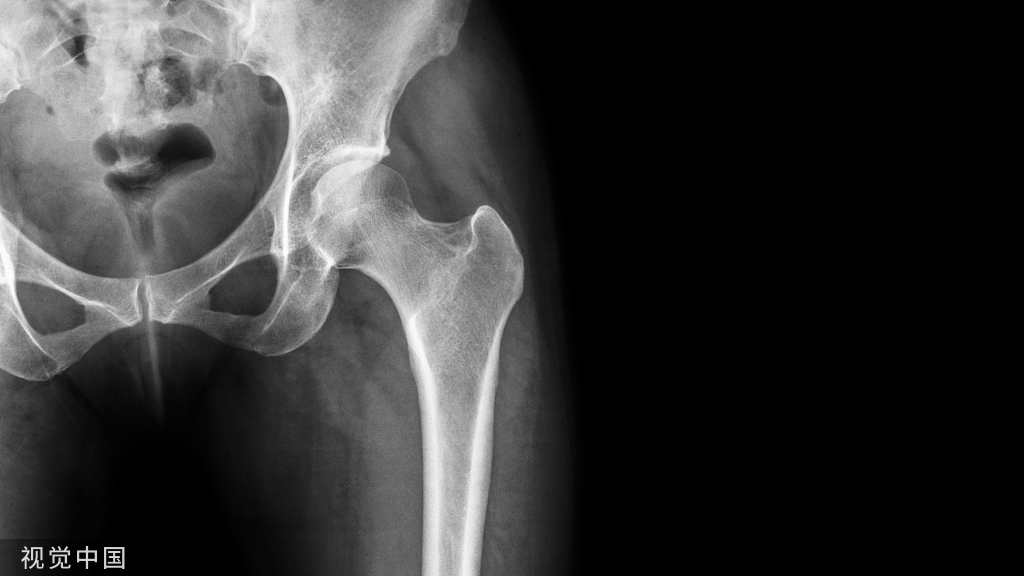

带线锚钉在膝关节的应用

应用范围:

• 侧副韧带的修复

• 交叉韧带止点撕脱骨折的修复

• 髌骨不稳等

1.带线锚钉治疗侧副韧带止点断裂

膝关节内侧副韧带(medial collateral ligaments,MCL)是膝关节内侧的主要稳定结构,膝关节外侧暴力常常导致其损伤。

2.带线锚钉治疗交叉韧带下止点骨折

前交叉韧带(anterior cruciate ligament,ACL)胫骨止点撕脱骨折实际上是一种特殊类型的ACL损伤,应早期修复,避免交叉韧带重建。

3.带线锚钉治疗髌骨不稳定

髌骨不稳由骨性解剖异常以及软组织限制性不足引起,目前多数学者主张积极手术治疗。

内侧髌股韧带(MPFL)是髌骨静力性稳定机制中最重要的结构,在治疗髌骨不稳的术式中,MPFL重建术是有效的手术方法之一。在MPFL重建技术中,髌骨侧的固定多数采用制作隧道固定,但存在易发生髌骨骨折的缺点。

带线锚钉法:采用髌骨端锚钉固定技术,对于发育不良的小髌骨患者,骨隧道技术极易导致髌骨骨折,锚钉同定技术不侵扰髌骨前方皮质,骨量丢失少,降低髌骨骨折的发生。